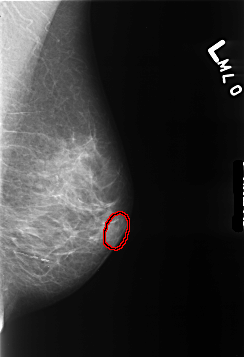

B_3445_1.LEFT_MLO

FILE: B_3445_1.LEFT_MLO.OVERLAY

TOTAL_ABNORMALITIES 1

ABNORMALITY 1

LESION_TYPE MASS SHAPE LYMPH_NODE MARGINS N/A

ASSESSMENT 2

SUBTLETY 3

PATHOLOGY BENIGN_WITHOUT_CALLBACK

TOTAL_OUTLINES 1

BOUNDARY